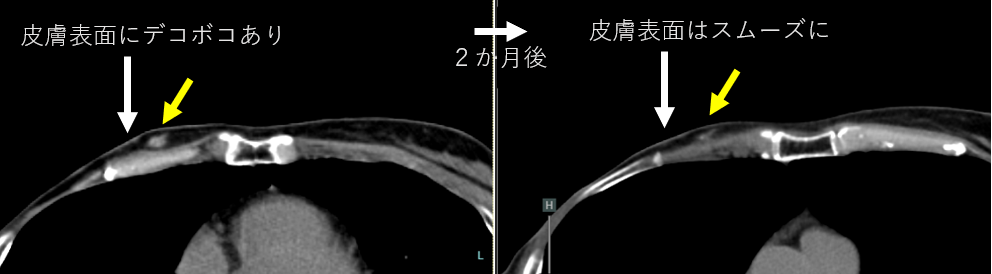

9月に行われた3例目の60日後の診察が行われました。本例はCTなどでみえるより、広い範囲でPETの集積が認められた患者さんです。MRI拡散強調画像では異常信号がなくなりました。またCTでは本人からも「触ってデコボコ感がなくなりました」と言葉をいただいております。

本研究では本人の自覚症状や拡散強調画像では効果判定は行わないため、また今後のMRIやCTで違う結果になる可能性があります。また現在のところいずれの患者さんでもGrade2までの副作用ですが、今後の過程では発生する可能性はあります。